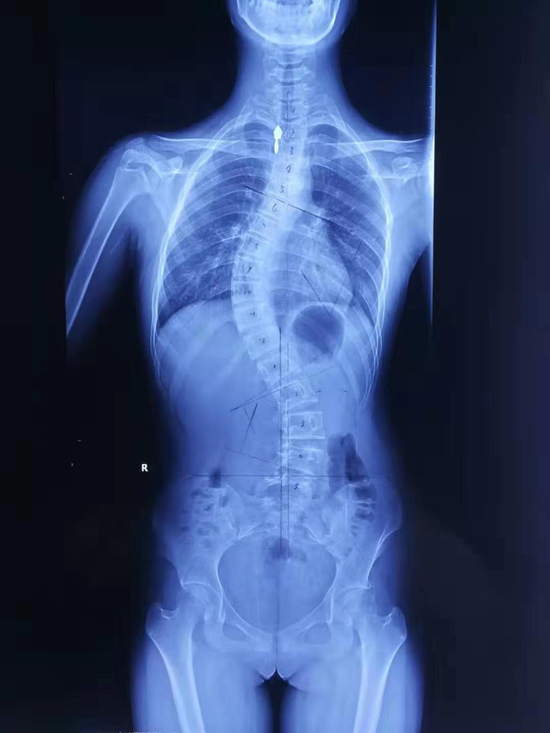

背部畸形图片,背部经络图片

犀利女孩后背畸形10年佛中医挑战高难度手术助其挺直腰杆

少女颈椎侧弯背部似"驼峰 哈市五院矫形手术助其又显亭亭玉立身

孩子背部突出没在意,结果拖到要动手术!

坐姿不当可致脊柱侧弯 脊柱畸形患者可享万元补贴